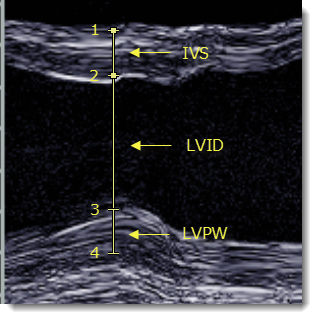

Χρησιμοποιήστε το εργαλείο Απόσταση LV για να μετρήσετε το μεσοκοιλιακό διάφραγμα (IVS), την εσωτερική διάσταση αριστερής κοιλίας (LVID) και το πάχος οπίσθιου τοιχώματος αριστερής κοιλίας (LVPW) σε εικόνες υπερηχογραφήματος M-mode.

2. Κάντε κλικ στο ένα άκρο του IVS για να τοποθετήσετε την πρώτη λαβή (1).

3. Κάντε κλικ στο άλλο άκρο του IVS για να τοποθετήσετε τη δεύτερη λαβή (2).

Εμφανίζεται το πάχος του IVS.

4. Κάντε κλικ στο ένα άκρο του LVPW για να τοποθετήσετε την τρίτη λαβή (3).

Εμφανίζεται το LVID.

5. Κάντε κλικ στο άλλο άκρο του LVPW για να τοποθετήσετε την τέταρτη λαβή (4).

Εμφανίζεται το πάχος του LVPW.